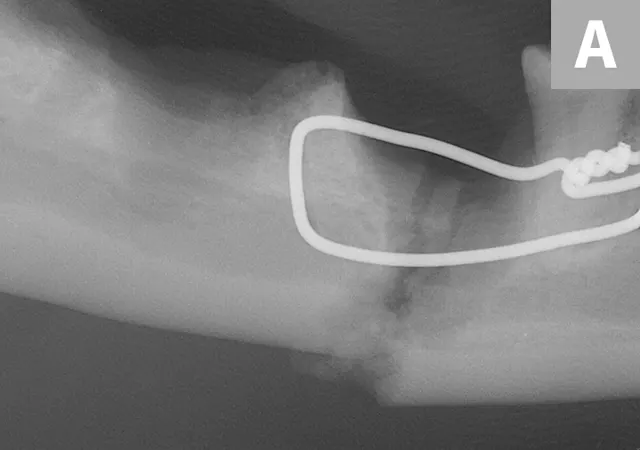

A complete oral examination confirmed stage 4 periodontal disease of numerous teeth (ie, first through fourth maxillary premolars, all maxillary molars, both maxillary canines, all remaining incisors). Dental radiographs confirmed bilateral mandibular fractures at the mesial root of the right mandibular first molar and distal root of the left mandibular first molar (Figures 1 and 2).

Preoperative intraoral dental radiographs of the right (A and B) and left (C) mandibular first molars. There is marked alveolar bone loss secondary to periodontal disease (blue lines), as well as pathologic, iatrogenic mandibular fractures (arrows).